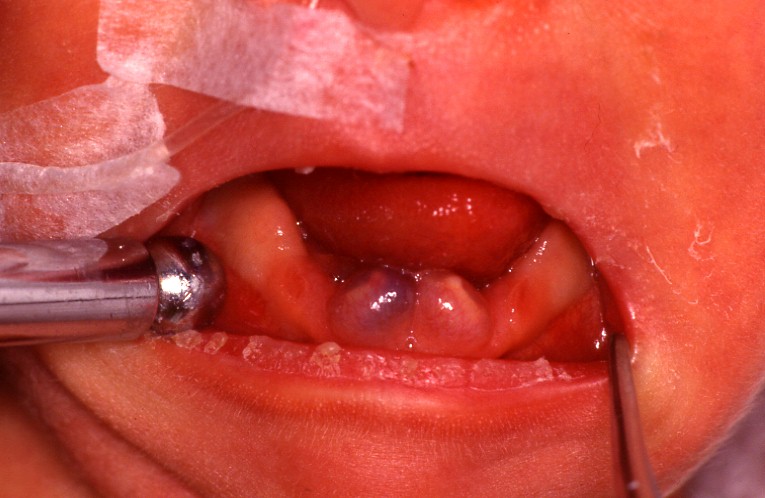

乳前歯の萌出時に発生した萌出嚢胞

歯が萌出中に当該歯槽堤粘膜に限局性の膨隆としてみられる嚢胞がまれに生ずることがある。

組織学的には含歯性嚢胞と同様の所見をもち、含歯性嚢胞に含まれるが、一般にこれを萌出嚢胞とよぶ。

治療法は開窓術であり、これにより歯の萌出が進み、嚢胞は消失する。

しかし多くの場合、歯の萌出とともに自然消退する事が多い。